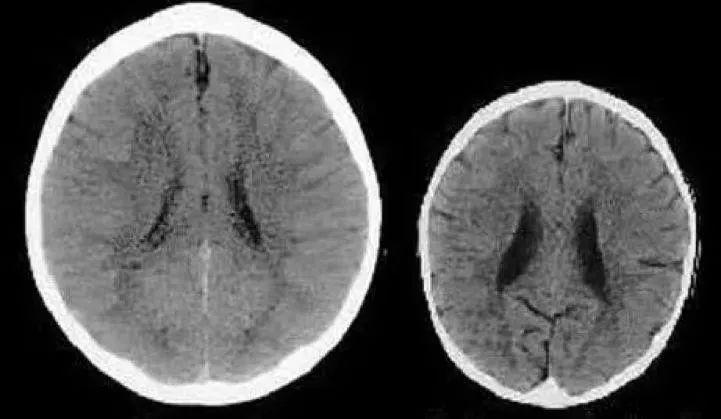

研究指出,經常被怒吼責罵的孩子,大腦的韋尼克區和前額葉之間的連接會減少,而大腦左側顳上回的灰質體積增值會達到14%,這意味着孩子的語言表達能力正在逐漸弱化,理解能力越來越差。

腦科學家洪蘭教授洪蘭教授也指出:核磁共振腦造影技術發現,經常被吼罵的孩子,海馬迴出現萎縮的現象,而這種萎縮會影響孩子的記憶力。